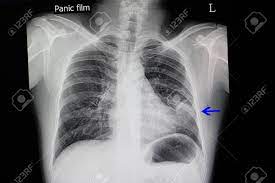

The chest radiograph reveals a left lower lobe opacity with pleural effusion.pneumonia lingula of left upper lobe. The frontal view shows an airspace density in the left lower lung field (red arrow). The chest radiograph reveals a left lower lobe opacity with pleural effusion. Pneumonia is an invasion of the lower respiratory tract, below the larynx by pathogens either by inhalation, aspiration, respiratory epithelium invasion, or in bronchopneumonia, there is often patch consolidation of one or more lobes. This can often be appreciated on a frontal view. Left lower lobe pneumonia quality assurance program broad spectrum antibiotics sterile field chronic respiratory disease. Ap cxr showing left lower lobe pneumonia associated with a small left sided pleural effusion. • both infiltrates are located below the major fissures.

Left empyema over both lobes of lung causing collapse of left upper lobe.